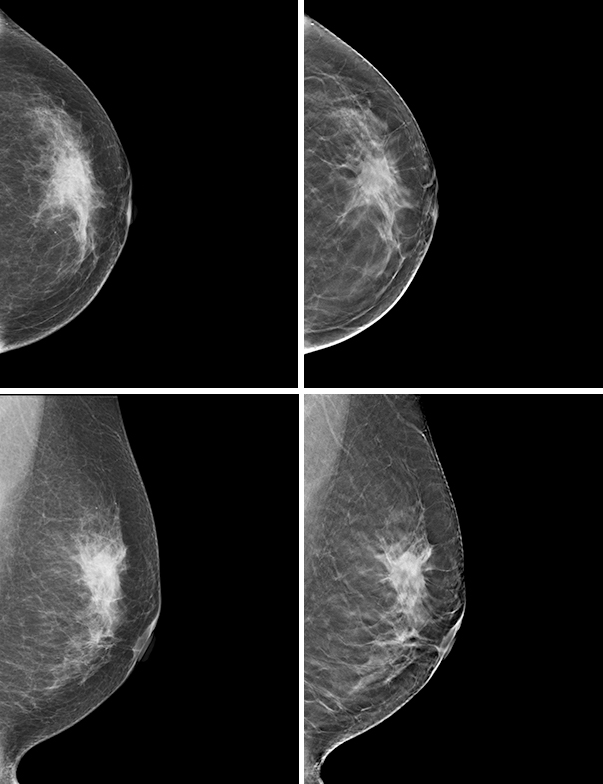

同一患者のLCC(上)とLMLO(下)。2D(左)に比べ,トモシンセシス(右)では

より明瞭に病変を確認可能(ホロジックジャパン提供)